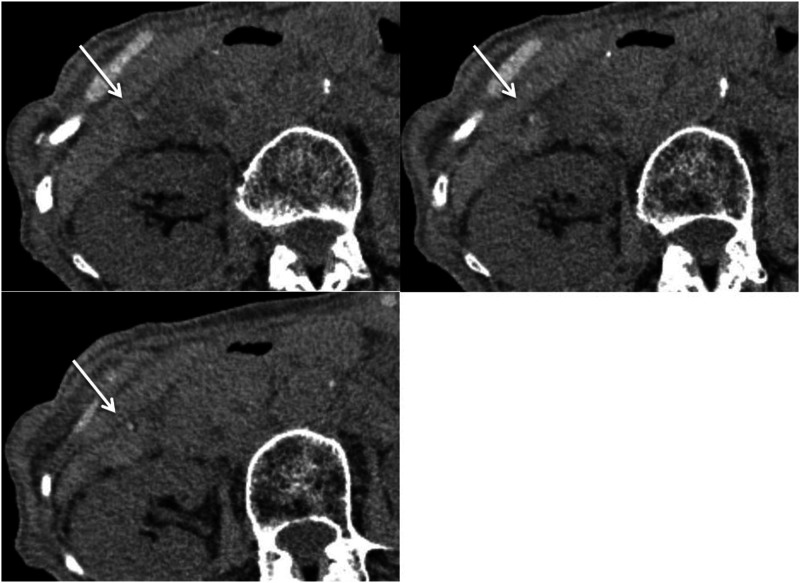

The purpose of this report was to evaluate the usefulness of hyperdense whirl sign on unenhanced computed tomography (CT) for diagnosing gallbladder torsion. The CT scans of seven patients with gallbladder torsion were independently reviewed by two board-certified radiologists for locating the high-density core with twisting between the gallbladder neck and liver bed, termed hyperdense whirl sign. The sign was observed in six cases. The detection of a hyperdense whirl sign on unenhanced CT appears useful for diagnosing gallbladder torsion.

Abstract Image